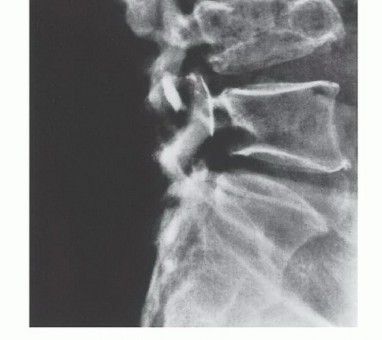

- Plain Radiography: The cornerstone of initial evaluation. It accurately predicts the diagnosis in over 80% of extremity bone tumors. It defines the lesion's location, zone of transition (narrow/sclerotic = benign/slow; wide/permeative = malignant/aggressive), cortical destruction, and periosteal reactions (Codman triangle, onion-skinning, sunburst pattern).

Sarcomas generally respect major anatomic boundaries, taking the path of least mechanical resistance. They initially expand within the specific anatomic compartment of origin (e.g., the anterior compartment of the thigh, or the medullary canal of a bone). Only in advanced stages, or following iatrogenic violation (e.g., a poorly planned biopsy), do they breach the compartment walls—such as thick muscular aponeuroses, fascia, or cortical bone—to invade adjacent compartments.

- Effective Barriers: Articular cartilage, dense cortical bone, and thick fascial septae are robust natural barriers to tumor extension.

Tumors are defined surgically as intracompartmental if they are entirely contained within their native anatomic compartment. They are extracompartmental if they have breached a fascial/cortical barrier, or if they originate in an uncompartmentalized space (e.g., the popliteal fossa, axilla, groin, or antecubital fossa). Most high-grade primary bone sarcomas are bicompartmental at presentation, having destroyed the native cortex via the Haversian and Volkmann canals to form a contiguous soft tissue mass. Carcinomas metastatic to the extremity, unlike primary sarcomas, ignore compartmental boundaries and exhibit true infiltrative growth.